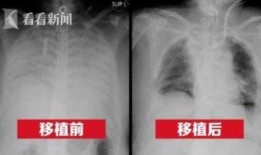

港媒最新爆料新冠肺病人,新冠肺病患者真实生活现状及挑战”

最近港媒可是爆出了一个大新闻,让人不禁瞪大了眼睛!说的是新冠肺病人的一些最新情况,听起来是不是有点刺激?那就跟着我一起,来揭开这...